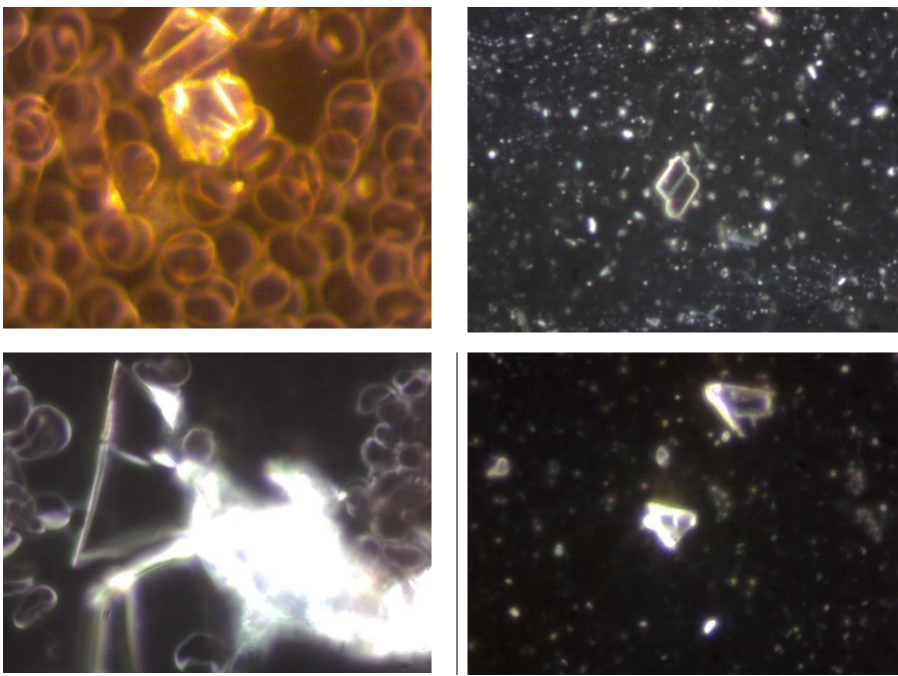

Comparison of crystals in the blood and in the vaccine; on the left, crystalline formations are found in the blood of test subjects vaccinated with Comirnaty (BioNTech/Pfizer), the images on the right show that these types of crystals are also found in Comirnaty vaccines. Image credit: Helen Krenn

In an article from The Expose entitled: Covid Injection Aftermath: Study finds 94% of “Vaccine” Recipients have Pre-Blood Clot Formations and Foreign Particles, by Rhonda Wilson, on 8/24/2022 the author states: An Italian study published two weeks ago in the International Journal of Vaccine Theory, Practice, and Research revealed almost everyone who had been injected had abnormalities after Covid vaXXXination. In 94% of vaXXXinated blood, there was an aggregation of red blood cells and the presence of particles of various shapes and sizes. The study began in March 2021. Using dark-field microscopy, the researchers analyzed blood samples from 1,006 referred to the Giovannini Biodiagnostic Centre for various disorders after being injected with Pfizer/BioNTech or Moderna mRNA vaccines.

In the study, authors noted that the vaccines are purported to contain at least the spike protein from SARS-CoV-2 but are known also to contain foreign particles. “Among those foreign components are metallic objects as demonstrated previously in this journal by Lee et al. (2022) which are confirmed in our results.” Of the 1,006 cases analyzed, only 58 – equal to 5.77% of the total – presented a completely normal hematological picture upon microscopic analysis after the last mRNA injection with either the Moderna or Pfizer vaccine. The blood of 948 – 94% of the study’s participants – showed aggregation of red blood cells and the presence of particles of various shapes and sizes of unclear origin one month after the mRNA injection.

Graphene Ferric oxide crystals (Ferromagnetic Properties) and Trypansoma cruzi parasite eggs were observed in the live capillary blood from a VAXXinated male using Brightfield, pHase contrast microscopy and confirmed with UV absorbance and Fluorescence Spectroscopy, Scanning Electron Microscopy, Transmission Electron Microscopy, Energy Dispersive Spectroscopy, X-ray Diffractometer and Nuclear Magnetic Resonance instruments. – Copyright Hikari Omni Media – Robert O. Young MSc, DSc, PhD, Naturopathic Practitioner – 2021